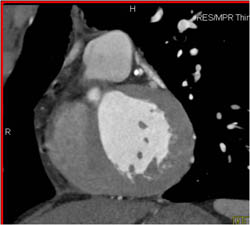

Greater Than 50% LAD Disease